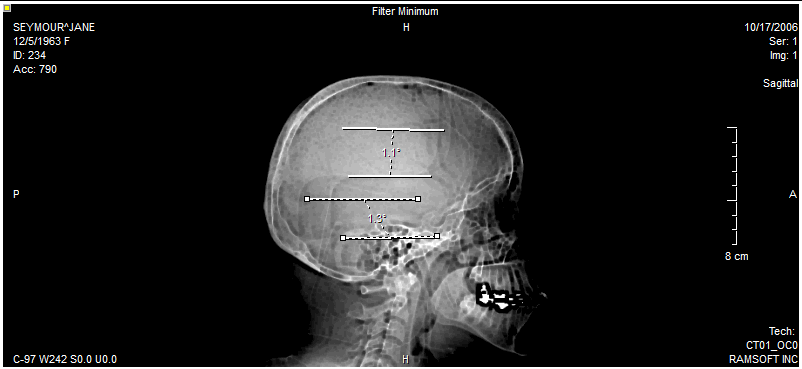

If the apex of the angle you need to measure is located off screen, the Cobb Angle tool can be used. This tool is accessible from the Angle tool pull-down menu.

This tool is used by placing four points on the image. The first two are the end points of one arm of the angle, and the other two belong to the second arm.

The picture below shows the Cobb angle tool being used to measure the angle between two vertebrae on an X-ray image.